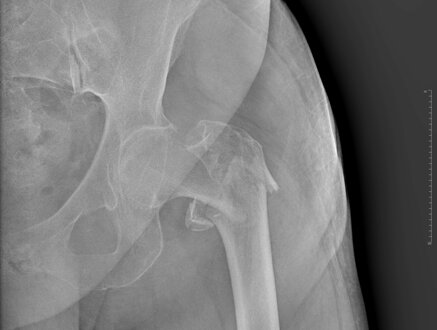

CLASSIFICAZIONE

Si dividono in:

• Laterali: sottotrocanteriche, pertrocanteriche, basicervicali

• Mediali: sottocapitata, transcervicale

L'indagine diagnostica principale per poter eseguire la diagnosi è la radiografia dell'anca, ma in alcuni casi, soprattutto nei casi di frattura ingranata, può esser necessaria l'esecuzione di una TC. Raramente la RM è utilizzata per la diagnosi.